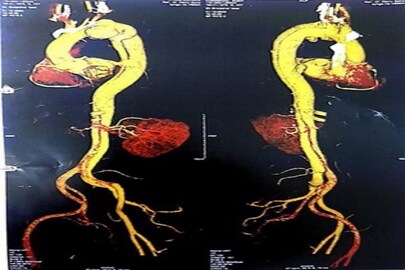

কলকাতা: হৃদযন্ত্রের মূল রক্ত সরবরাহকারী ধমনী ছিঁড়ে যাওয়ার পরও সেটাকে মেরামত করে প্রাণ ফিরিয়ে দিল দক্ষিণ কলকাতার একটি বেসরকারি হাসপাতাল।এই ধরনের অস্ত্রোপচার দক্ষিণ কলকাতায় একটি নজির গড়ল। যাকে এক কথা বলে 'টাইপ বি অর্টিক ডিসেকশন'।

৩রা জানুয়ারি নিউ ব্যারাকপুরে সুজন চৌধুরী(৪৩) শ্বাসকষ্ট এবং কাশির সঙ্গে রক্ত ক্ষরণ নিয়ে ওই বেসরকারি হাসপাতালে ভর্তি হন।সুজন বাবুর শারীরিক অবস্থা বেশ জটিল ছিল।ডাক্তারবাবুরা তার শারীরিক পরীক্ষা-নিরীক্ষা করে জানতে পারে তাঁর হৃদপিন্ডের 'টাইপ বি অর্টিক নার্ভ' ছিঁড়ে গেছে।সেখান থেকে রক্ত ক্ষরণ হচ্ছে।ওই নালিটি ১০০ শতাংশ ব্লক ছিল।অবস্থা এতটাই গুরুতর ছিল যে,সঙ্গে সঙ্গে অপারেশনের সিদ্ধান্ত নিতে হয়েছিল ডাক্তারদের।

অপারেশন থিয়েটারে নিয়ে যাওয়ার পর ফুসফুস ও হৃদপিণ্ড একটি কৃত্রিম মেশিনের সঙ্গে যুক্ত করে দেন চিকিৎসকরা। শুধু তাই নয়, হৃদপিন্ডের যে নালিটি ক্ষতিগ্রস্ত হয়েছিল,সেটিতেও একটি কৃত্রিম নালির প্রতিস্থাপন করেন তাঁরা। অপারেশনের সময় হৃদপিণ্ডটিকে তিন ঘন্টা যাবত স্থবির করে রাখা হয়েছিল।একটি মেশিনের দ্বারা হার্ট এবং ফুসফুসকে ৭ ঘন্টা ধরে চালিত রেখেছিল।অবশেষে সুজন চৌধুরীর অপারেশন সফল হয়। এই বিষয়ে আর এন টেগোর হাসপাতালের কার্ডিয়াক সার্জেন অতনু সাহা বলেন, ' অর্টিক্ ডিসেকশন একটি খুব জটিল বিষয় এবং এই রোগীর জন্য এটি আরও বেশি জটিল ছিল।এটি একটি 'টাইপ বি ডিসেকশন' ছিল।তবে খুব তাড়াতাড়ি সিদ্ধান্ত নেওয়ার ফলে প্রয়োজনীয় সাপোর্টে রোগীর অপারেশন সফলভাবে করা গিয়েছে।'

নিউ ব্যারাকপুর এলাকার বাসিন্দা সুজন চৌধুরী। গত৬ মাস আগে তাঁর মোটর বাইক দুর্ঘটনা হয়েছিল।সে সময় তিনি আহত হয়েছিলেন।তবে তার সঙ্গে এই টাইপ বি ডিসেকশন এর কোন সম্পর্ক নেই। প্রতিটি মানুষের হৃদপিন্ডের টাইপ ওয়ান ধমনীটি ক্ষতিগ্রস্থ হয়।এক্ষেত্রে টাইপ বি ক্ষতিগ্রস্থ হওয়াটা বেশ আশ্চর্য্য লেগেছে ডাক্তারদের কাছে।এটাও ডাক্তার অতনু সাহার কাছে একটি বড় চ্যালেঞ্জ ছিল বলে দাবি হাসপাতাল কতৃপক্ষের। তবে রোগী আস্তে আস্তে স্বাভাবিকের দিকে আসছে। দাবী ডাক্তারদের।